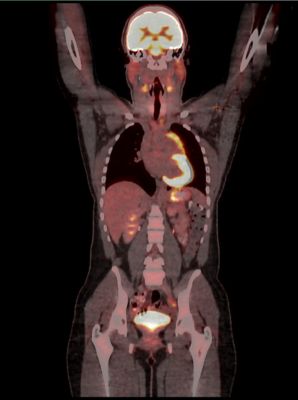

ПЭТ-КТ (pet-ct) — эффективный и современный метод диагностики онкологических заболеваний, сочетающий позитронно-эмиссионную (ПЭТ) и компьютерную томографию (КТ) .

Так что же такое ПЭt-kt? Метод представляет собой комбинацию двух видов диагностических исследований - позитронно-эмиссионной томографии (ПЭТ) и компьютерной томографии (КТ) .

Сначала делают компьютерную томографию (КТ), затем - позитронно-эмиссионную томографию (ПЭТ) . В среднем, первое исследование длится две минуты, второе - до получаса . Обе процедуры проводят . . .

20 интересных фактов о ПЭТ/КТ . 9 . Диагностика ПЭТ/КТ выявляет опухоли на более ранних стадиях, чем КТ или МРТ, потому что метаболические нарушения можно зафиксировать тогда, когда структурные изменения еще отсутствуют .

Что такое ПЭТ КТ? ПЭТ КТ (позитронно-эмиссионная томография) - метод обследования, предназначенный для обнаружения заболеваний невралгического характера, раковых опухолей и проблем сердечно-сосудистой системы .